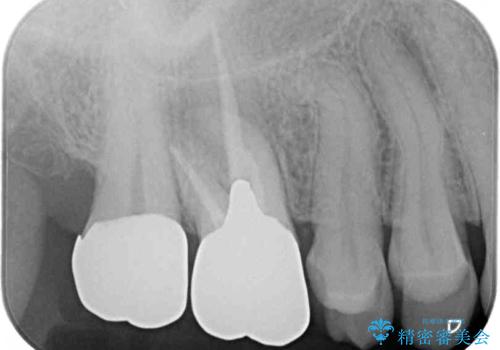

大臼歯では、根管治療後にも痛みが残ってしまったため、外科的歯内療法(歯根端切除術)を適用しました。外科処置直後は腫れや痛みなどがありましたが、半年が経過し、痛みがなくなり、レントゲン写真上でも炎症の消退が認められました。